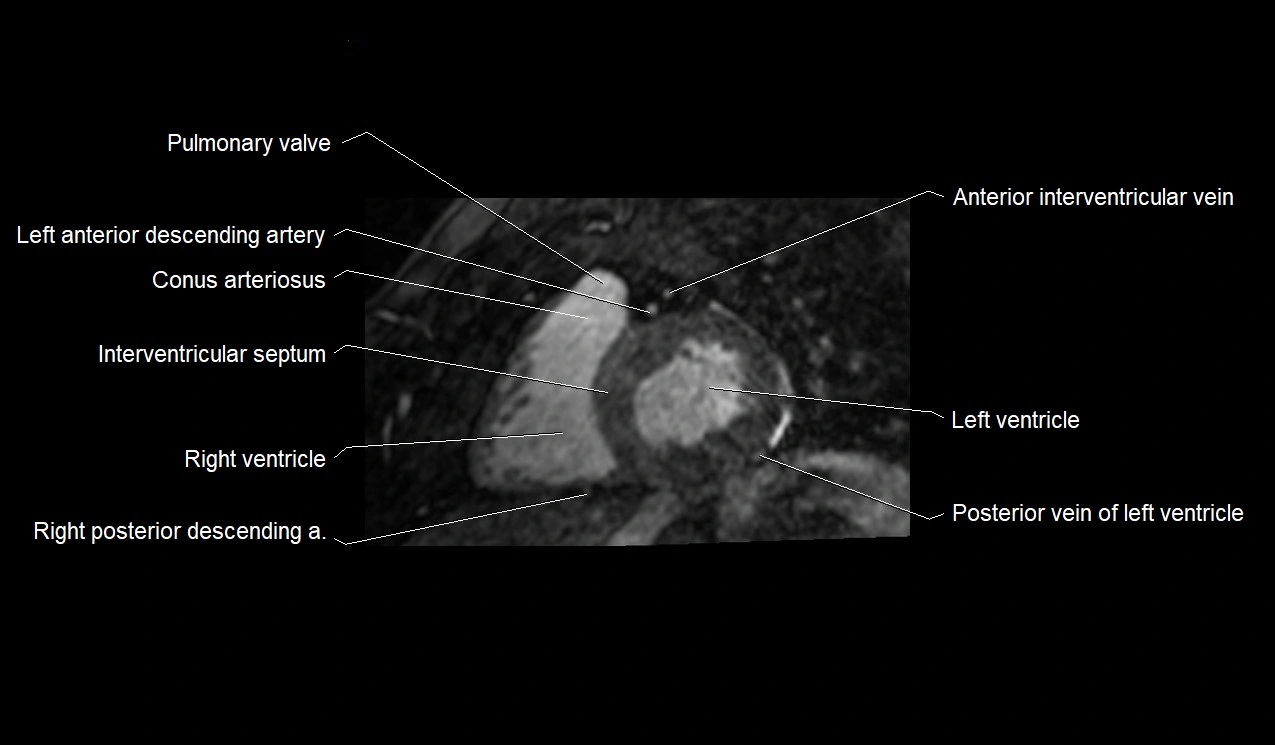

MRI image